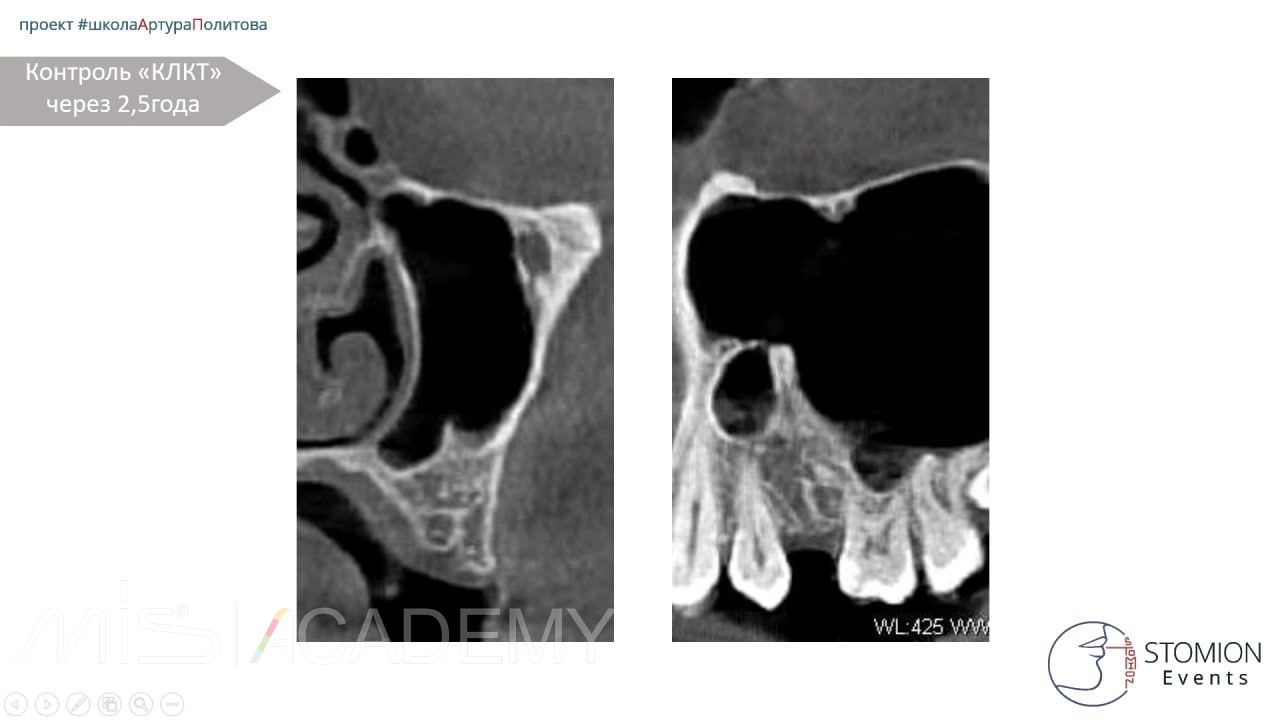

Далее пациентка пропала с радаров. Через 2,5 года на КЛКТ мы видим полное восстановление костной ткани, восстановление синуса. Это очередная победа декомпрессии над привычными методами.